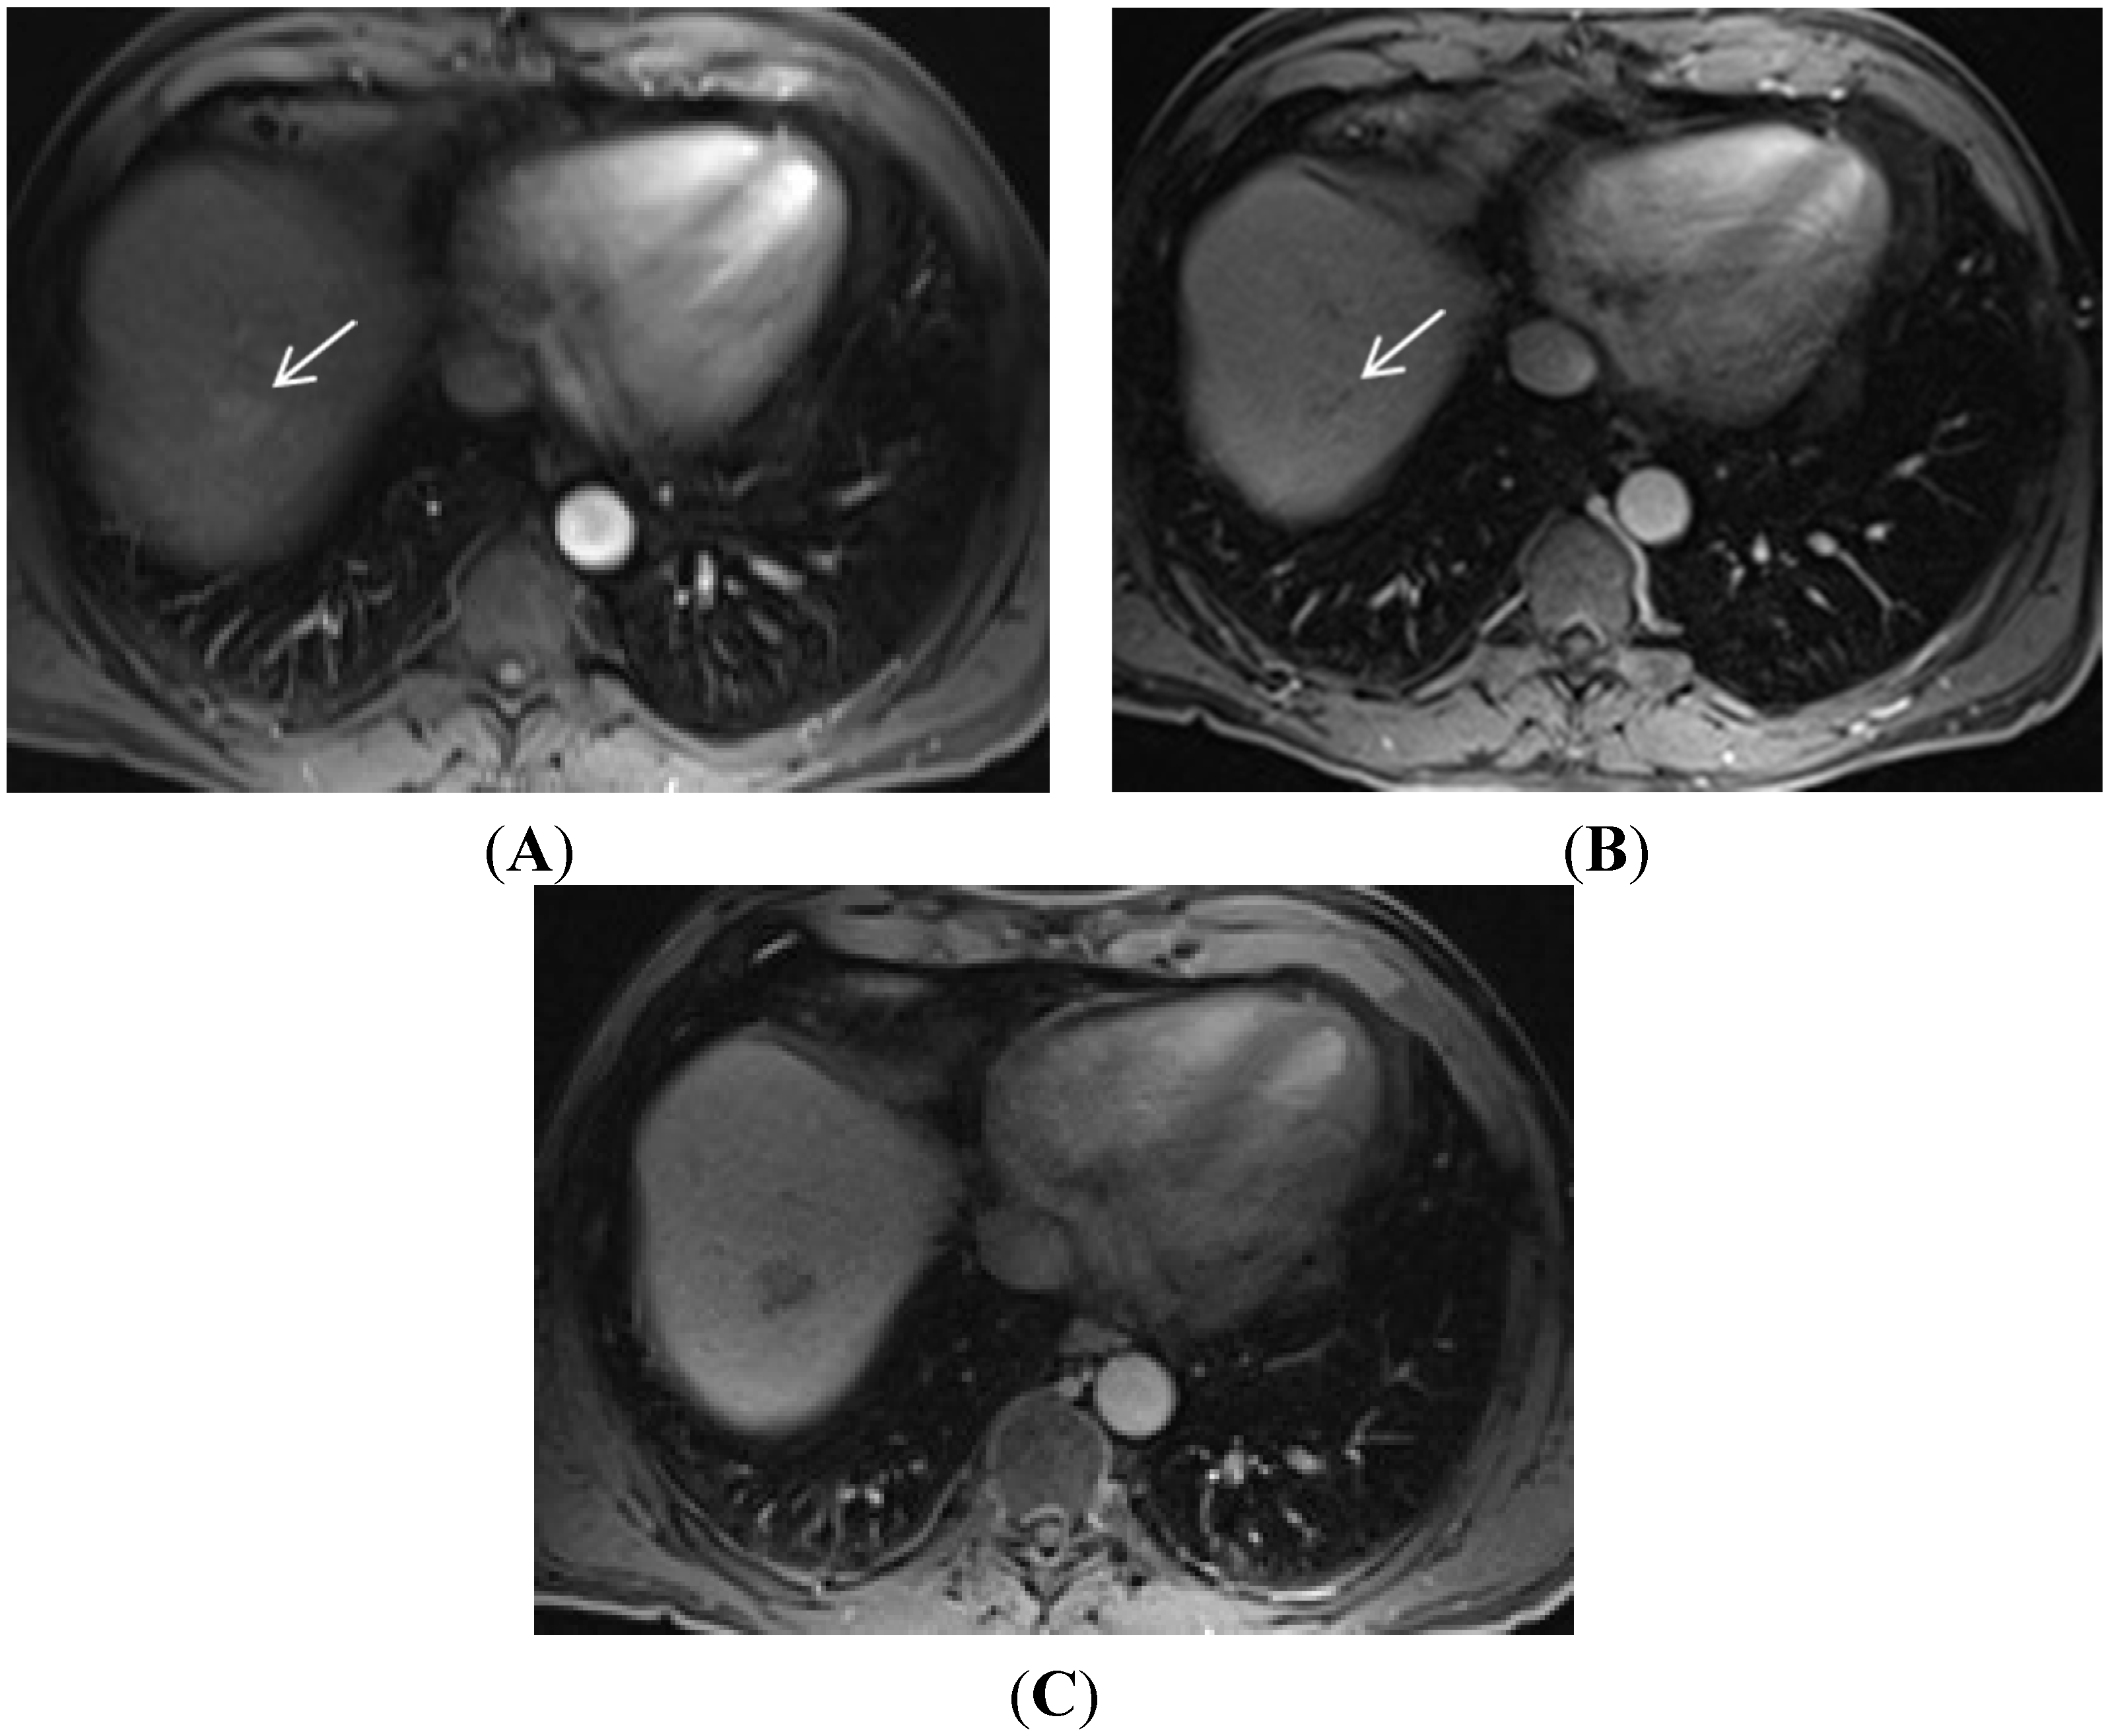

- Ishigami, K.; Yoshimitsu, K.; Nishihara, Y.; Irie, H.; Asayama, Y.; Tajima, T.; Nishie, A.; Hirakawa, M.; Ushijima, Y.; Okamoto, D.; et al. Hepatocellular carcinoma with a pseudocapsule on gadolinium-enhanced MR images: Correlation with histopathologic findings. Radiology 2009, 250, 435–443. [Google Scholar] [CrossRef] [PubMed]

- Yu, J.S.; Rofsky, N.M. Dynamic subtraction mr imaging of the liver: Advantages and pitfalls. Am. J. Roentgenol. 2003, 180, 1351–1357. [Google Scholar] [CrossRef] [PubMed]

- Hecht, E.M.; Holland, A.E.; Israel, G.M.; Hahn, W.Y.; Kim, D.C.; West, A.B.; Babb, J.S.; Taouli, B.; Lee, V.S.; Krinsky, G.A. Hepatocellular carcinoma in the cirrhotic liver: Gadolinium-enhanced 3D T1-weighted MR imaging as a stand-alone sequence for diagnosis. Radiology 2006, 239, 438–447. [Google Scholar] [CrossRef] [PubMed]

- Choi, J.Y.; Lee, J.M.; Sirlin, C.B. CT and MR imaging diagnosis and staging of hepatocellular carcinoma: Part I. Development, growth, and spread: Key pathologic and imaging aspects. Radiology 2014, 272, 635–654. [Google Scholar] [CrossRef] [PubMed]